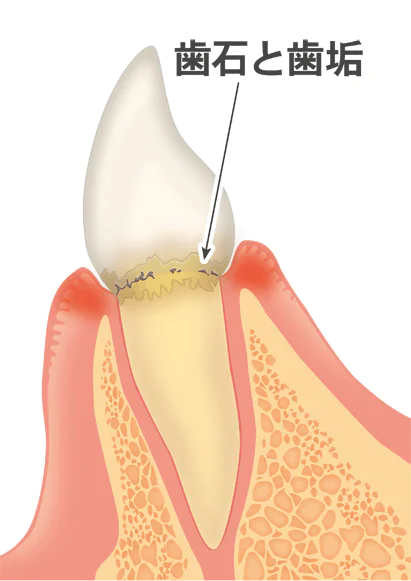

歯周病の主な原因はプラークと呼ばれる歯垢です。プラークは歯と歯ぐきの間に形成され、乳白色の粘性のある物で、中には歯周病やむし歯の原因となる細菌が集まっています。

1mgのプラークには約10億もの細菌が含まれているとされています。時間の経過とともに、プラークはバイオフィルムとして強固な集合体へと変化します。

このバイオフィルムは唾液の殺菌作用を避け、歯周病やむし歯の進行を促進します。歯垢の効果的な予防と管理は、歯科衛生の基本であり、日常的な歯磨きや定期的な歯科検診が重要です。

スケーリング

超音波や手用のスケーラーを用いて、歯石やプラークを除去し、歯周ポケット内を清掃する手法です。特に軽度から中等度の歯周炎に対する一般的な治療法です。

超音波や手用のスケーラーを用いて、歯石やプラークを除去し、歯周ポケット内を清掃する手法です。特に軽度から中等度の歯周炎に対する一般的な治療法です。